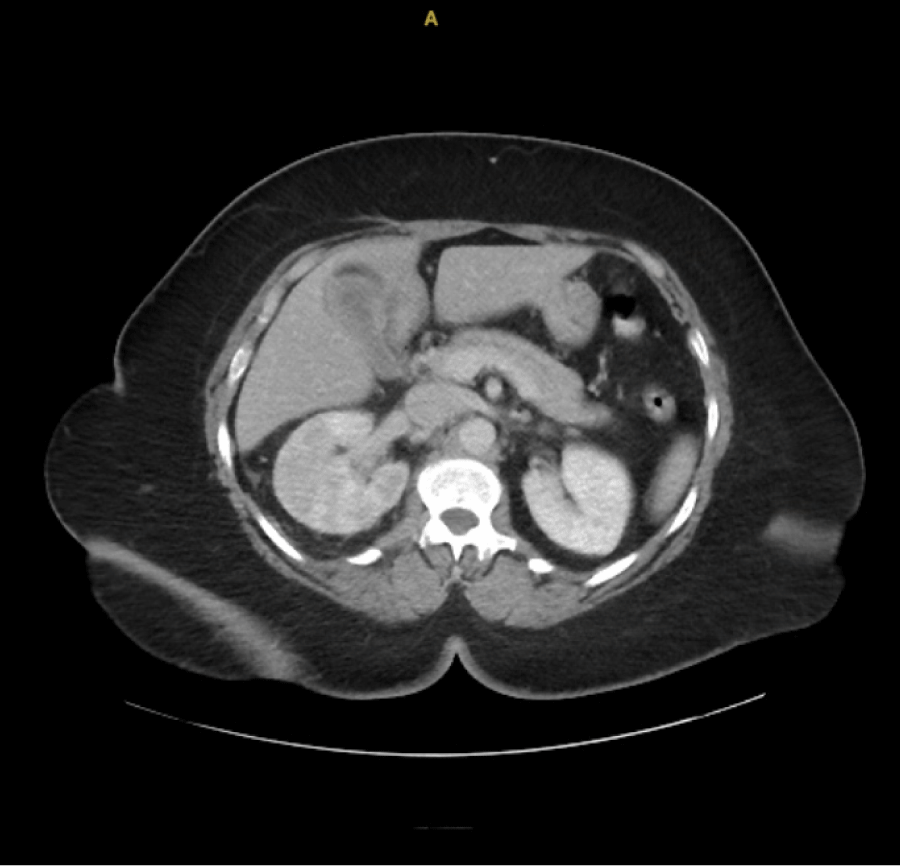

The patient was started on IV ceftriaxone and fluids. Urology was consulted, Infectious Disease and Nephrology were consulted. Blood cultures grew E. coli (2/2 bottles). Urology performed cystoscopy with ureteral stent placement, confirmed fluoroscopically (Figure 3). Infectious Disease recommended ceftriaxone 2 g IV daily.

Figure 3: Intraoperative fluoroscopy image confirming placement of a right ureteral stent (arrowhead). View Figure 3